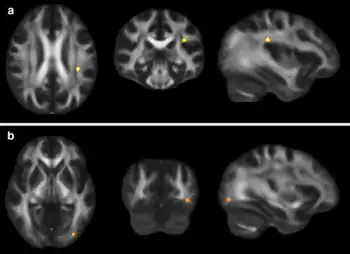

Increased diffusion on MRI is associated with the severity of post-concussive symptoms | |